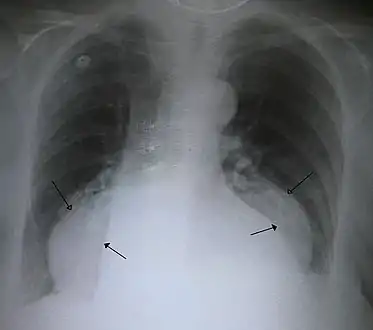

Diagnosis

The diagnosis of a hiatal hernia is typically made through an upper GI series, endoscopy, high resolution manometry, esophageal pH monitoring, and computed tomography (CT). Barium swallow as in upper GI series allows the size, location, stricture, stenosis of oesophagus to be seen. It can also evaluate the oesophageal movements. Endoscopy can analyse the esophageal internal surface for erosions, ulcers, and tumours.

Meanwhile, manometry can determine the integrity of esophageal movements, and the presence of esophageal achalasia. pH testings allows the quantitative analysis of acid reflux episodes. CT scan is useful in diagnosing complications of hiatal hernia such as gastric volvulus, perforation, pneumoperitoneum, and pneumomediastinum.[8]